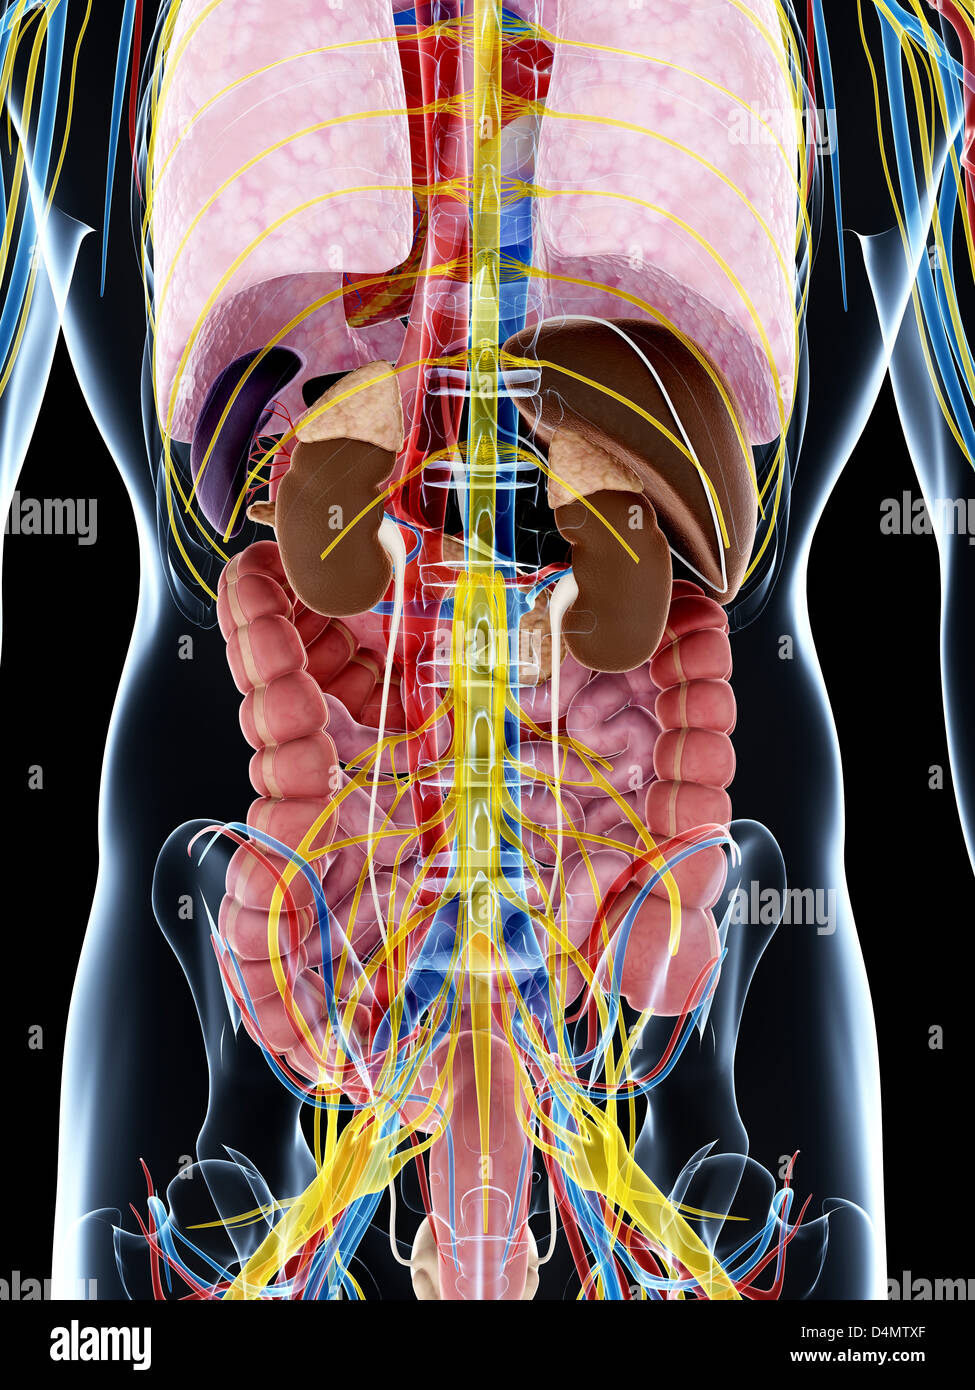

RF2GB8D4J–3D-Darstellung des Verdauungssystems der männlichen Anatomie, zusammen mit anderen inneren Organen. Glasbild auf blauem Hintergrund, Vorderansicht.